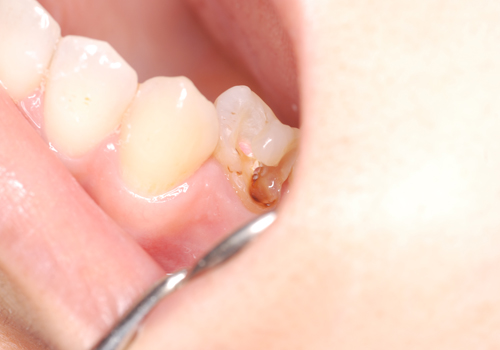

(左:肉眼、右:マイクロ使用)

(上:肉眼、下:マイクロ使用)

徹底的な感染源(虫歯)の除去

まずは感染源となる虫歯を徹底的に除去することから始まります。ここで重要なのはできる限り虫歯の部分だけを削り、健康な歯の部分を保存することです。そのためには非常に精密な手技が必要になりますが、ただでさえ小さい歯の中でそれを肉眼で達成することは難しく、対象物を最大20倍までに拡大することができるマイクロスコープを使うことが必要になります。

| 治療内容 | 右下の前から5番目の銀歯の歯茎に瘻孔という膿の出口が確認できます。 レントゲンでは根っこの先が黒く抜けており、膿が溜まっている状態でした。また歯の神経の管が1つ治療がされていないように見えます。被せ物と中の土台を外したところ大きな虫歯が確認できました。徹底的に虫歯を除去し、ラバーダム防湿下で根管治療を行いました。 術後のレントゲンで黒い影が小さくなっている、また治療前にあった歯茎の瘻孔が消失したことが確認できたため、ファイバーコアによって土台を作り、セラミッククラウンによる被せ物を装着致しました。 |